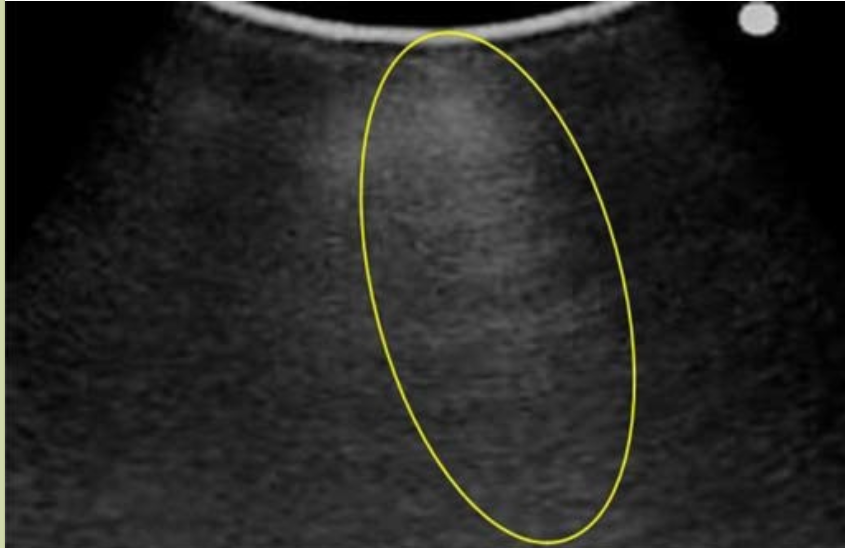

正常肺脏超声影像学特点

新生儿正常肺组织在超声下呈低回声。在B型超声下,胸膜线与A-线均呈清晰、光滑、规则的线性高回声(光滑、清晰、规则),彼此等间距平行排列,由肺野浅部入深A-线回声逐渐减弱至消失;无(出生3~7 d后)或可有少数几条B线(生后3~7 d内),但无AIS、胸腔积液和肺实变等超声征象;在实时超声下可见肺滑,在M型超声下则表现为沙滩征